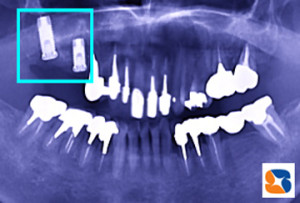

コラム「2本のインプラントをレントゲンで確認」の画像